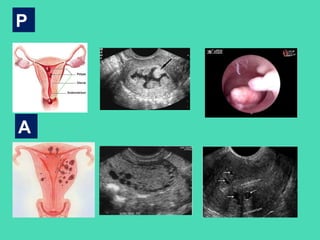

P

A

• PALM representa las alteraciones estructurales del útero.

COEIN representa las alteraciones no estructurales.

Basados en la terminología y patología propuesta, esta

clasificación muestra una primera parte descriptiva y otra

etiológica. Por ej., AUB-P corresponde a Hemorragia uterina

anormal-Pólipo.

Adicionalmente, en el caso de los Miomas, se desarrolla una

clasificación específica, con énfasis especial en los miomas

submucosos. De esta manera, la clasificación puede llevar puntos

adicionales, por ej., AUB/HMB-MSm0 corresponde a Hemorragia

uterina anormal/Sangrado menstrual abundante –

Mioma submucoso tipo 0.